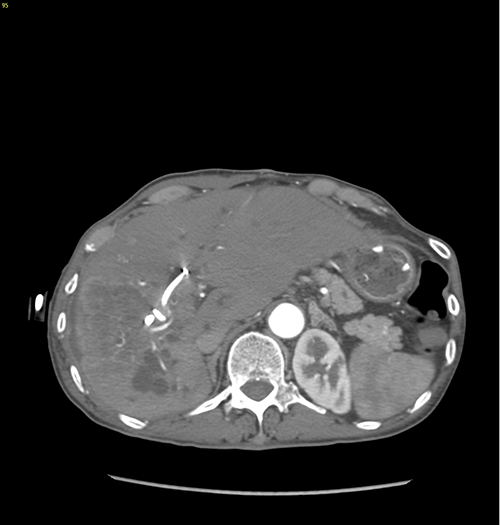

右肝胆管细胞癌、胆道梗阻---右三肝切除、左肝管空肠Roux-en-Y切除